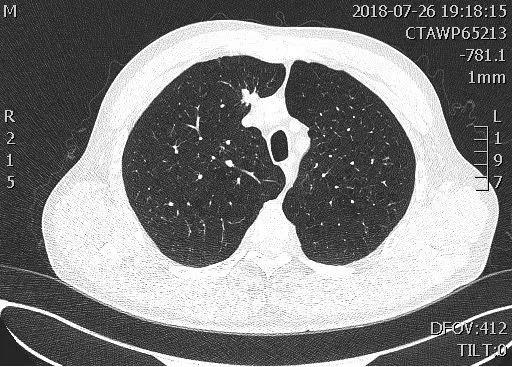

2018年9月,影像科引进推想人工智能辅助筛查系统,它是最智能的“CT室医生”,它可以在5秒之内读完患者的胸部CT片,并能将可疑部位进行自动标注。在我国,肺癌是发病率、死亡率最高的恶性肿瘤,在所有的恶性肿瘤当中,肺癌患者的5年生存率也是最低的,仅为17%,很多患者发现罹患肺癌时已是晚期,因此,肺癌的早发现、早治疗就显得尤为重要。要想早期发现肺癌可以进行肺结节筛查。而推想人工智能诊断系统对肺结节的发现辨识率高达99%,医生读片的结果也可以用它进行进一步核实。它与影像科诊断医生携手作战让肺结节筛查更加高效、精准。

影像科宫敬主任评价道:“推想人工智能肺结节筛查系统发现结节能力很强,还可以判断结节性质,位置因素等等,测量结节相比于人工测量更加准确,可以给医生更好的参考。”

影像科陈雷主任评价道:“有些微小结节医生用肉眼观察可能会忽略掉,但使用推想软件筛查,极大的提高了结节的检出率,提高了早期肺癌的筛查,辅助医生更加高效准确的完成胸部报告书写”。

影像科诊断医师焦桥对AI人工智能诊断系统的看法:“在针对胸膜下,心影及纵隔旁等部位的隐蔽结节人工阅片易漏诊,有了推想的辅助,有效地减少了此类结节的漏诊,且对结节的良恶性有提示。”

该病例结节位于右肺上叶纵隔旁,医生表示属于易漏诊区域,但推想AI系统给出了很清晰的标注,并提示为高危结节,后经手术证实为腺癌。

推想人工智能筛查系统已经“学习”了40多万经过专业医师标记的胸部CT结节信息,在扫描胸部CT后它会像人一样来“阅”片,与医生相结合,从而在筛查肺结节方面达到高效、精准、不漏诊的效果,更好地为患者服务。